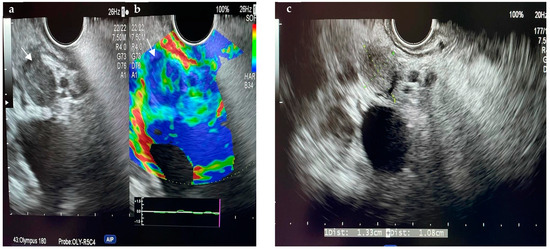

6.3.1. Ultrasound (US)

6.3.2. Abdominal Contrast-Enhanced Ultrasound (CEUS)

6.4.1. Endoscopic Ultrasound (EUS)